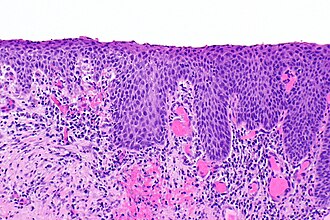

| Caption = | | Caption = Penile intraepithelial neoplasia. [[H&E stain]]. | ||

Image: Penile intraepithelial neoplasia -- intermed mag.jpg | PeIN - intermed. mag. | |||

Penile intraepithelial neoplasia. H&E stain. | |

Penile intraepithelial neoplasia, abbreviated PeIN, is the precursor of squamous cell carcinoma of the penis.